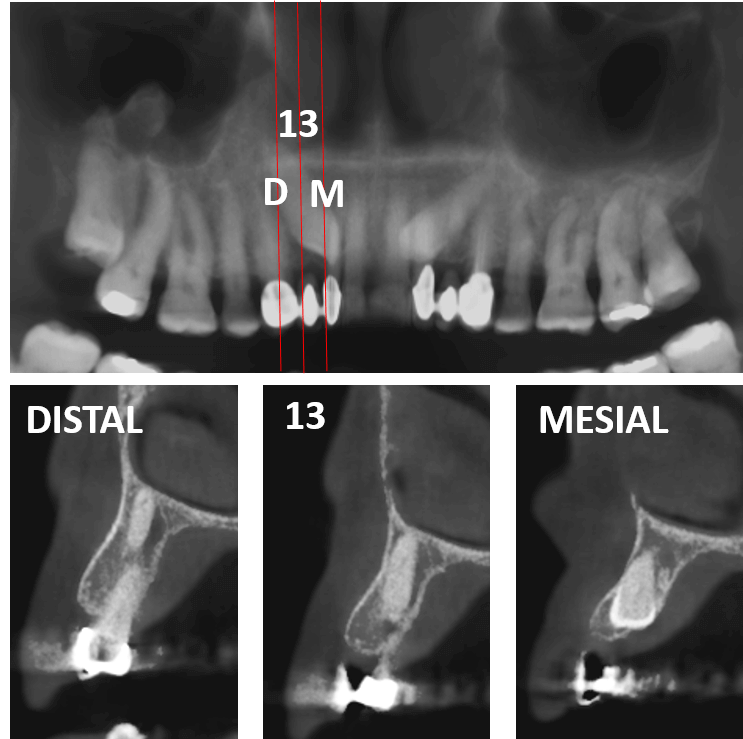

Fig.1

En la evaluación con tomografía computarizada cone beam, se realizó la reconstrucción panorámica del maxilar superior y los cortes transaxiales del órgano dentario 13 (Fig.1), el cual se observa impactado en posición mesioangular con su ápice radicular en relación con el piso de las fosas nasales y la corona en relación con la tabla ósea palatina. Asi mismo, se observa la impactación del canino contralateral (OD 23).